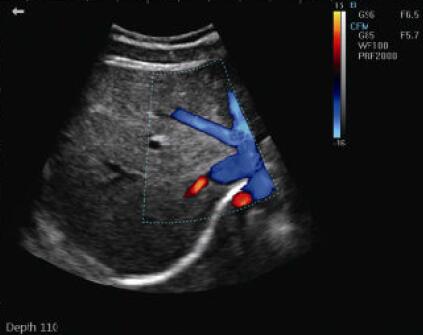

Image mode : 4B; M,B/M; CFM; PDI; PW; THI

Video Report Portable Color Doppler Machine Ultrasound Scanner System With 2 Probe Connector

| Operation Mode | 4B; M,B/M; CFM; PDI; PW; THI |

| Color flow mode(CFM) | |

| Power Doppler mode(PDI) | |

| Pulsed-wave Doppler(PW) | |

Video Report Portable Color Doppler Machine Ultrasound Scanner System With 2 Probe Connector Images |